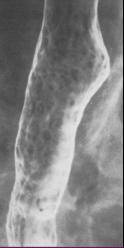

TOGD en double de

contrast |

Images claires

arrondies diffuse le long de oesophage . Mouvement

de contraction oesophagien normale . |